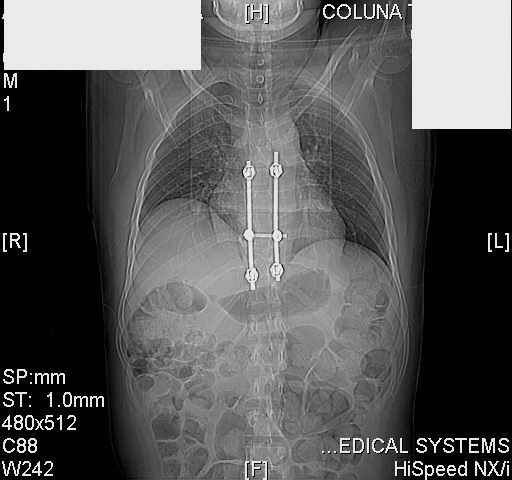

dear all (George?) Got a note this morning requesting an opinion about a patient 25 yrs froma remote area of the country who received this "excellent" stabilization of a fracturedthoracic spine over a year ago.The original neurosurgeon liberated the patient for fullactivities and rehab etc.The rehab doc wants to know what to do. Looks to me like the patientwas screwed pretty good! any offers?

Tom, Harrington rods from a medical museum, with industrial strength screws from a boatbuilder. What are the current symptoms?

Interesting case. Findings on CT: all four pedicle screws have been placed improperly inthat they miss the vertebral bodies. In addition, the screws on the left side are impingingon the decending thoracic aorta. What I do NOT know is the nature of the original injury, orwhether or not that injury has resolved. I would recommend removal of the hardware. I don'tthink it's a good idea to leave those screws where they are. If the original fracture ishealed, nothing else needs to be done.

dear Mark, all the details are not yet available but the patient is coming to see us foradvice. We probably will see him in the early new year. i thought that the 4th picture showedthe screw to enter the aorta? He is a victim of a motor vehicle crash and thoracic vertebralfracture which appears healed. He was posteriorly decompressed and this device inserted. asyou say there isno evidenece that any of the fixation enters the bodies via the pediclesistead they have passed thru and their end are no where near where they ought to be. If I amcorrect (I would prefer not to be) the aortic intima has been breached by the screw. When thetime comes to take the screw out I thought we should have control of the aorta.What do you think?

Tom: I strongly doubt that the aorta is involved. When these screws are put in, they firstput in a probe, then a tap, then the screw. If the aorta was punctured, they would have knownat the time. You might call the original surgeon (if in fact he is a real doctor) and get hisfeedback. The additional morbidity of a prophylactic thoracotomy would be a higher pricethan I would be willing to subject my patient to. Besides, it would be exceptionallydifficult to control the aorta at this point, especially if you tried to specifically getenough control to be able to put sutures in the back wall. Of course, difficulty of doingsomething isn't necessary a reason not to do it if you think it is necessary. I just think itis highly unlikely that the aorta is injured. I showed the case to both a thoracic surgeon anda neurosurgeon. The thoracic surgeon suggested getting an arteriogram to see if the aorta isinvolved. The neurosurgeon agreed that the hardware should be removed.

Mark Thank you. He is scheduled for a angio prior to transfer here. I keep going back to lookat that fourth image and although it is tough to believe the wall of the aorta seems toencompass the distal 1/2 of the screw. I have come to anticipate mal postion of screws thathave been inserted in hospitals that perhaps may not have the highest quality of equipment,including the human and radiological components. That having been said this case seems tosurpass the usual... one screw out of place or screwed into a disc etc. BTW I am notsuggesting that the screw was placed directly into the aorta but that moviment, pulse actionetc may have caused it to transgress the normal anatomical bounds without evident hemorrhage.